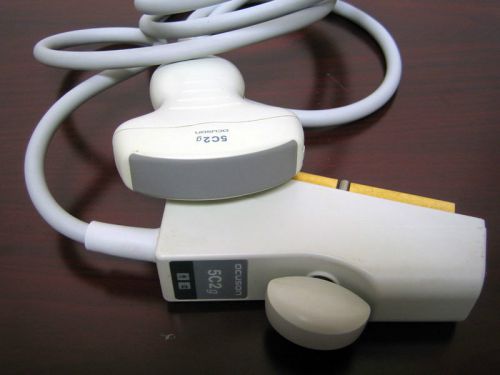

SIEMENS ACUSON Ultrasound Convex Transducer 5C2g Probe